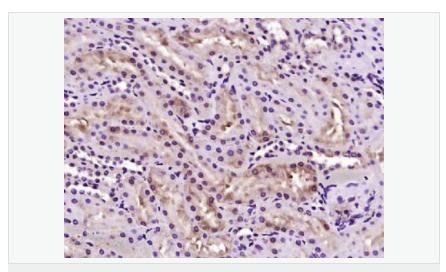

| 英文名稱(chēng) | LULL1/TOR1AIP2 |

| 中文名稱(chēng) | LULL1蛋白抗體 |

| 產(chǎn)品應用 | WB=1:500-2000 ELISA=1:5000-10000 IHC-P=1:100-500 IHC-F=1:100-500 ICC=1:100-500 IF=1:100-500 (石蠟切片需做抗原修復) not yet tested in other applications. optimal dilutions/concentrations should be determined by the end user. |

| 分 子 量 | 51kDa |

| 細胞定位 | 細胞核 細胞漿 |

| 免 疫 原 | KLH conjugated synthetic peptide derived from human LULL1:221-320/470 |

| 產(chǎn)品介紹 | LULL1 is a 470 amino acid endoplasmic reticulum single-pass membrane protein belonging to the TOR1AIP family. LULL1 interacts with torsinA, an essential AAA+ ATPase found in the endoplasmic reticulum (ER) and nuclear envelope (NE) of higher eukaryotes. LULL1 regulates the distribution and activity of torsinA within the ER and NE lumen and reveals functional defects in mutant torsinA, which is responsible for DYT1 dystonia, a neurodevelopmental disease caused by an in-frame deletion (Deltagag) in the gene encoding torsinA. The gene encoding LULL1 maps to human chromosome 1, which spans 260 million base pairs, contains over 3,000 genes and comprises nearly 8% of the human genome. Function: Regulates the distribution of TOR1A between the endoplasmic reticulum and the nuclear envelope. Subunit: Interacts with TOR1A and TOR1B (ATP-bound). Subcellular Location: Endoplasmic reticulum membrane; Single-pass membrane protein. Nucleus membrane. SWISS: Q8NFQ8 Gene ID: 163590 Database links: Entrez Gene: 163590 Human Omim: 614513 Human SwissProt: Q8NFQ8 Human Important Note: This product as supplied is intended for research use only, not for use in human, therapeutic or diagnostic applications. |